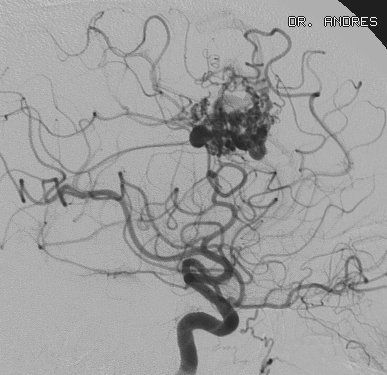

MALFORMACIONES CEREBROVASCULARES

Una malformación cerebrovascular es un grupo anormal de vasos sanguíneos en el cerebro que se forman de manera incorrecta. Estas malformaciones pueden afectar arterias, venas o ambos, lo que provoca que el flujo sanguíneo en el cerebro sea anormal. Debido a la estructura inusual de estos vasos, las malformaciones cerebrovasculares pueden ser propensas a sangrar, lo que aumenta el riesgo de hemorragia cerebral, convulsiones o daños neurológicos.